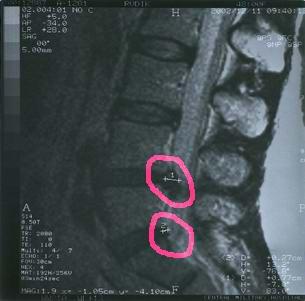

grija1.jpgПример1: В декабре 2002 г. проведено лечение больной, 1954 г. рождения, с грыжами диска поясничного отдела двух локализаций. На томограмме видно не только выраженные изменения в диске с пролобированием грыжи, но и сужение спиномозгового канала. Была яркая неврологическая картина в виде онемения в левой ноге, боли в икре, ладыжках, внизу живота, скованность, слабость в ногах (больше в левой), боли в копчике, жжение и круглосуточный болевой синдром. Лечили вытяжением, приемами мануальной терапии, медикаментозная терапия, но все эти действия не приводили к улучшению, а наоборот усугубили состояние. По нашей методике после первой же процедуры могла уже сидеть на жестком стуле, после 5-ой ходить и ездить в общественном транспорте. Всего получила 8 процедур и все болевые и неврологические симптомы исчезли.

На сегодняшний день (октябрь 2003) больная чувствует себя очень хорошо (работает на даче, выполняет все домашние работы, никаких жалоб и неврологических проявлений нет).

На снимке отчетливо видны две грыжи дисков в поясничном отделе,

значительно суживающие просвет спинномозгового канала.

Рекомендовано оперативное лечение.